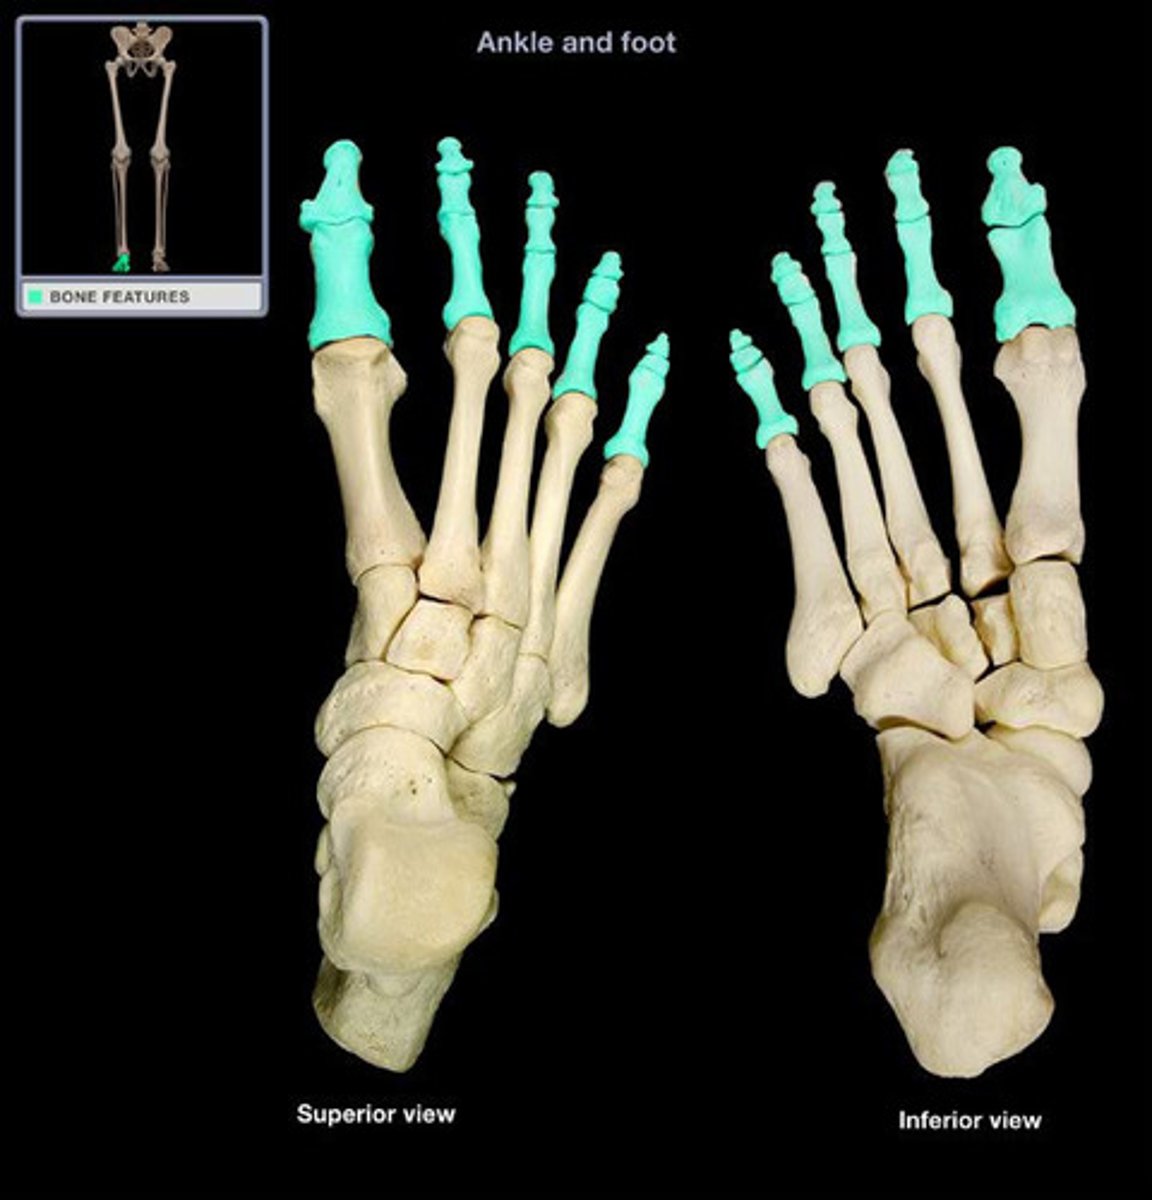

Phalanges (foot)

What (in general) do you call these bones